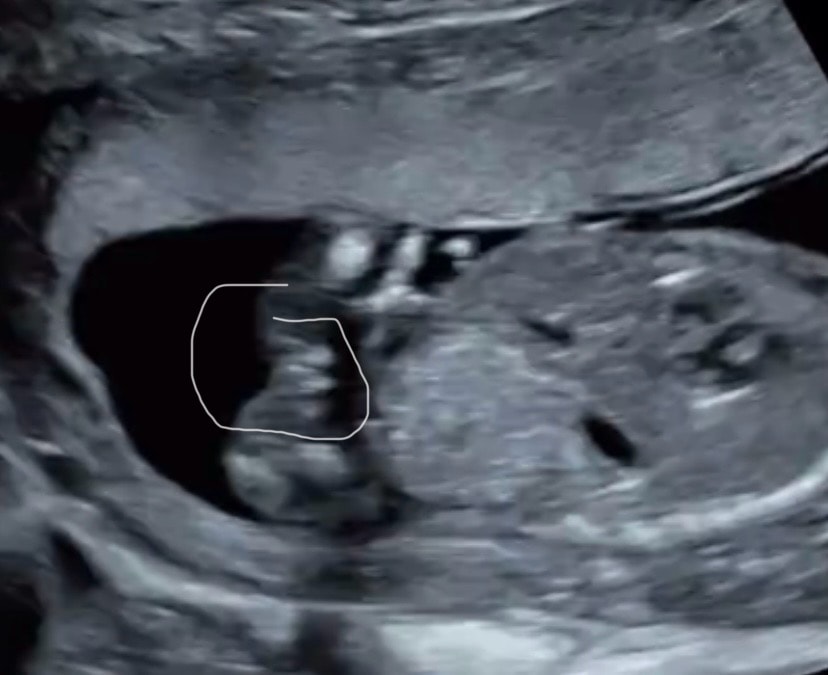

УЗИ 16-17 недель

это девочка на 99%

Мне кажется девочка

Мне тоже кажется, что это девочка )

❆Elena❆, да я уверена была, сын. Уже и кое что ему купила… теперь в мае спрошу. Изображение Вот наверху дочка моя, внизу сейчас. Изображение А еще вот. Девочки мне сказали губы и клитор торчит